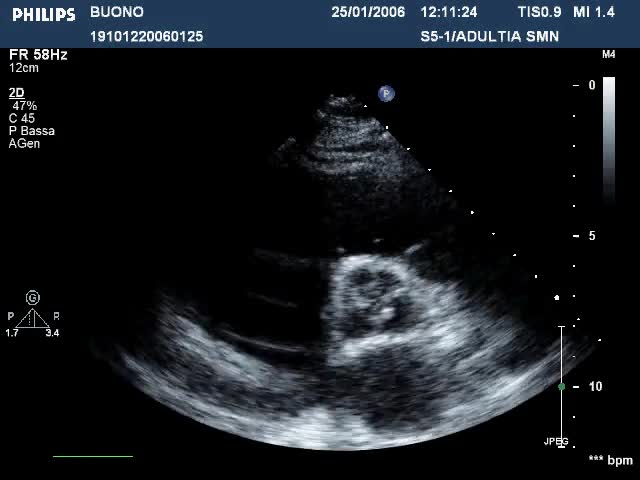

La diagnosi di Tako-Tsubo o Apical Balloning. La cardiomiopatia da stress